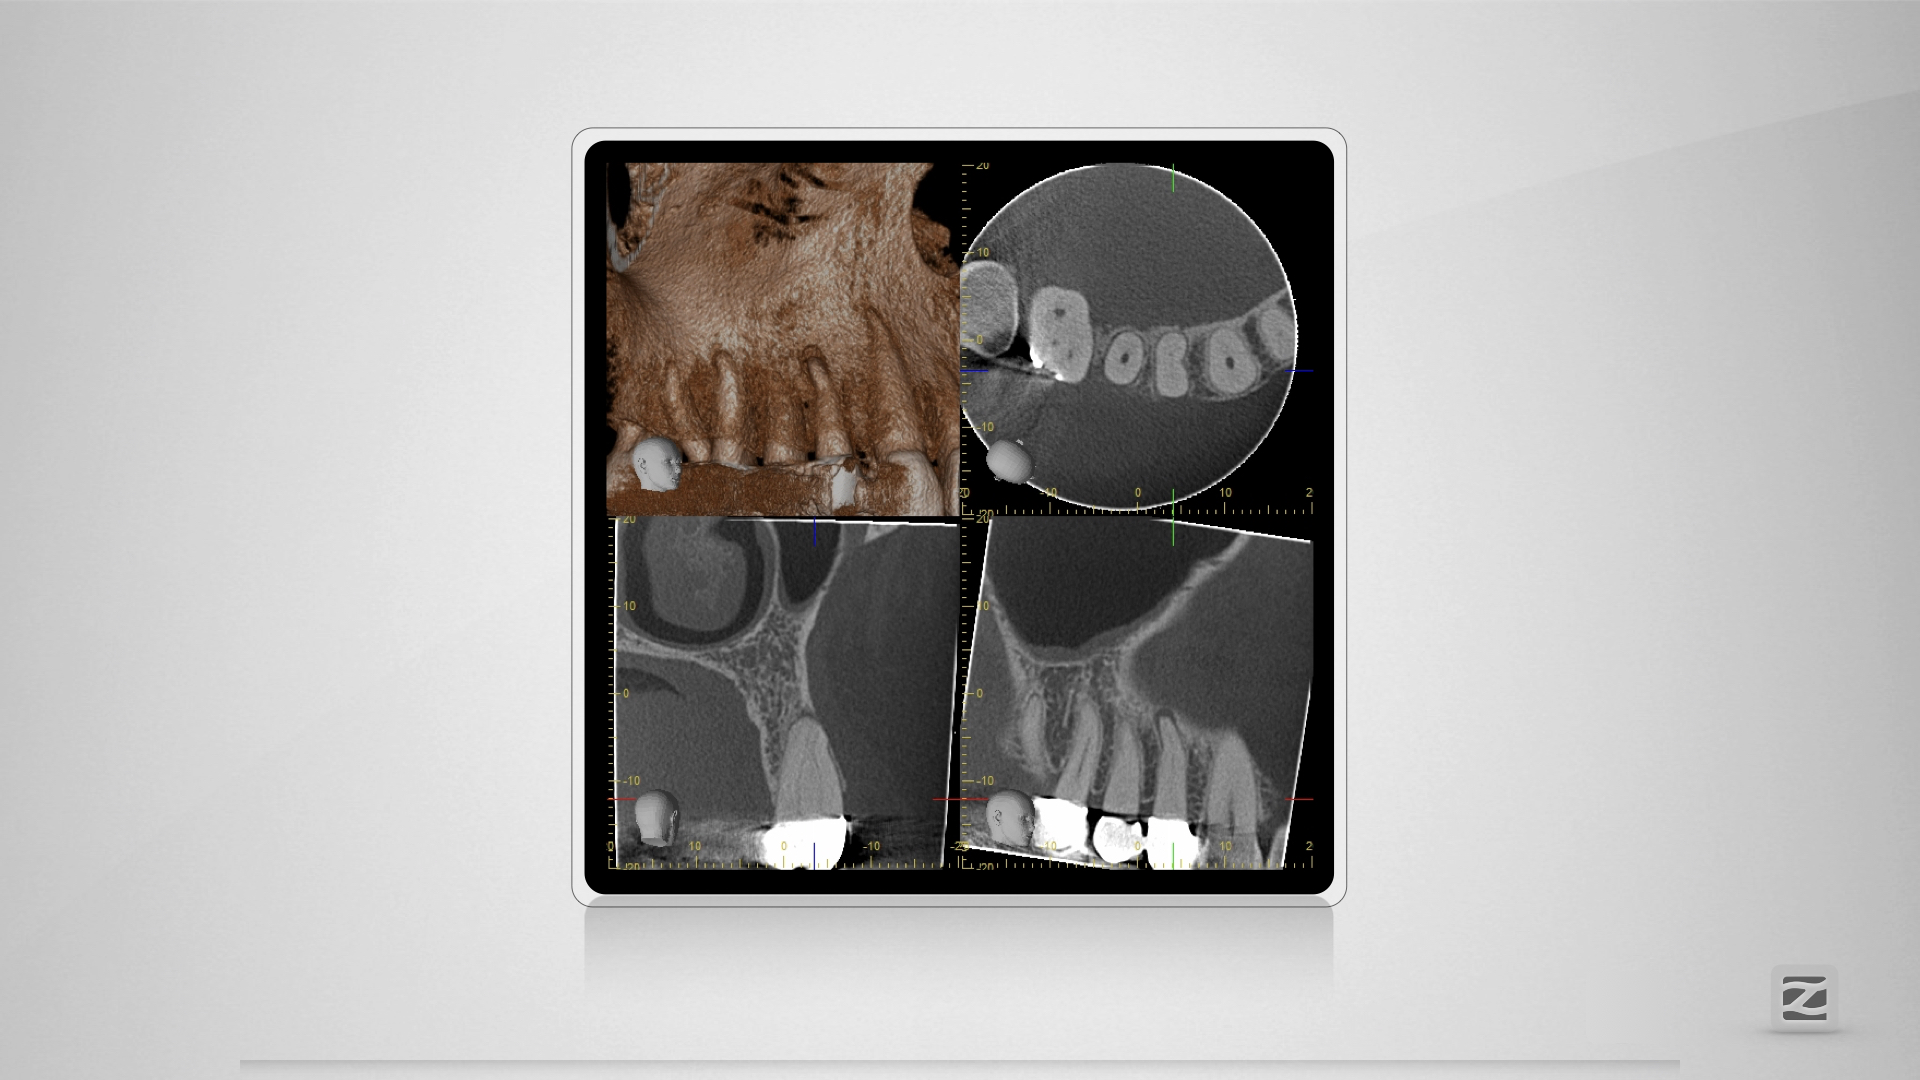

14D.002

H mit kleiner Tücke